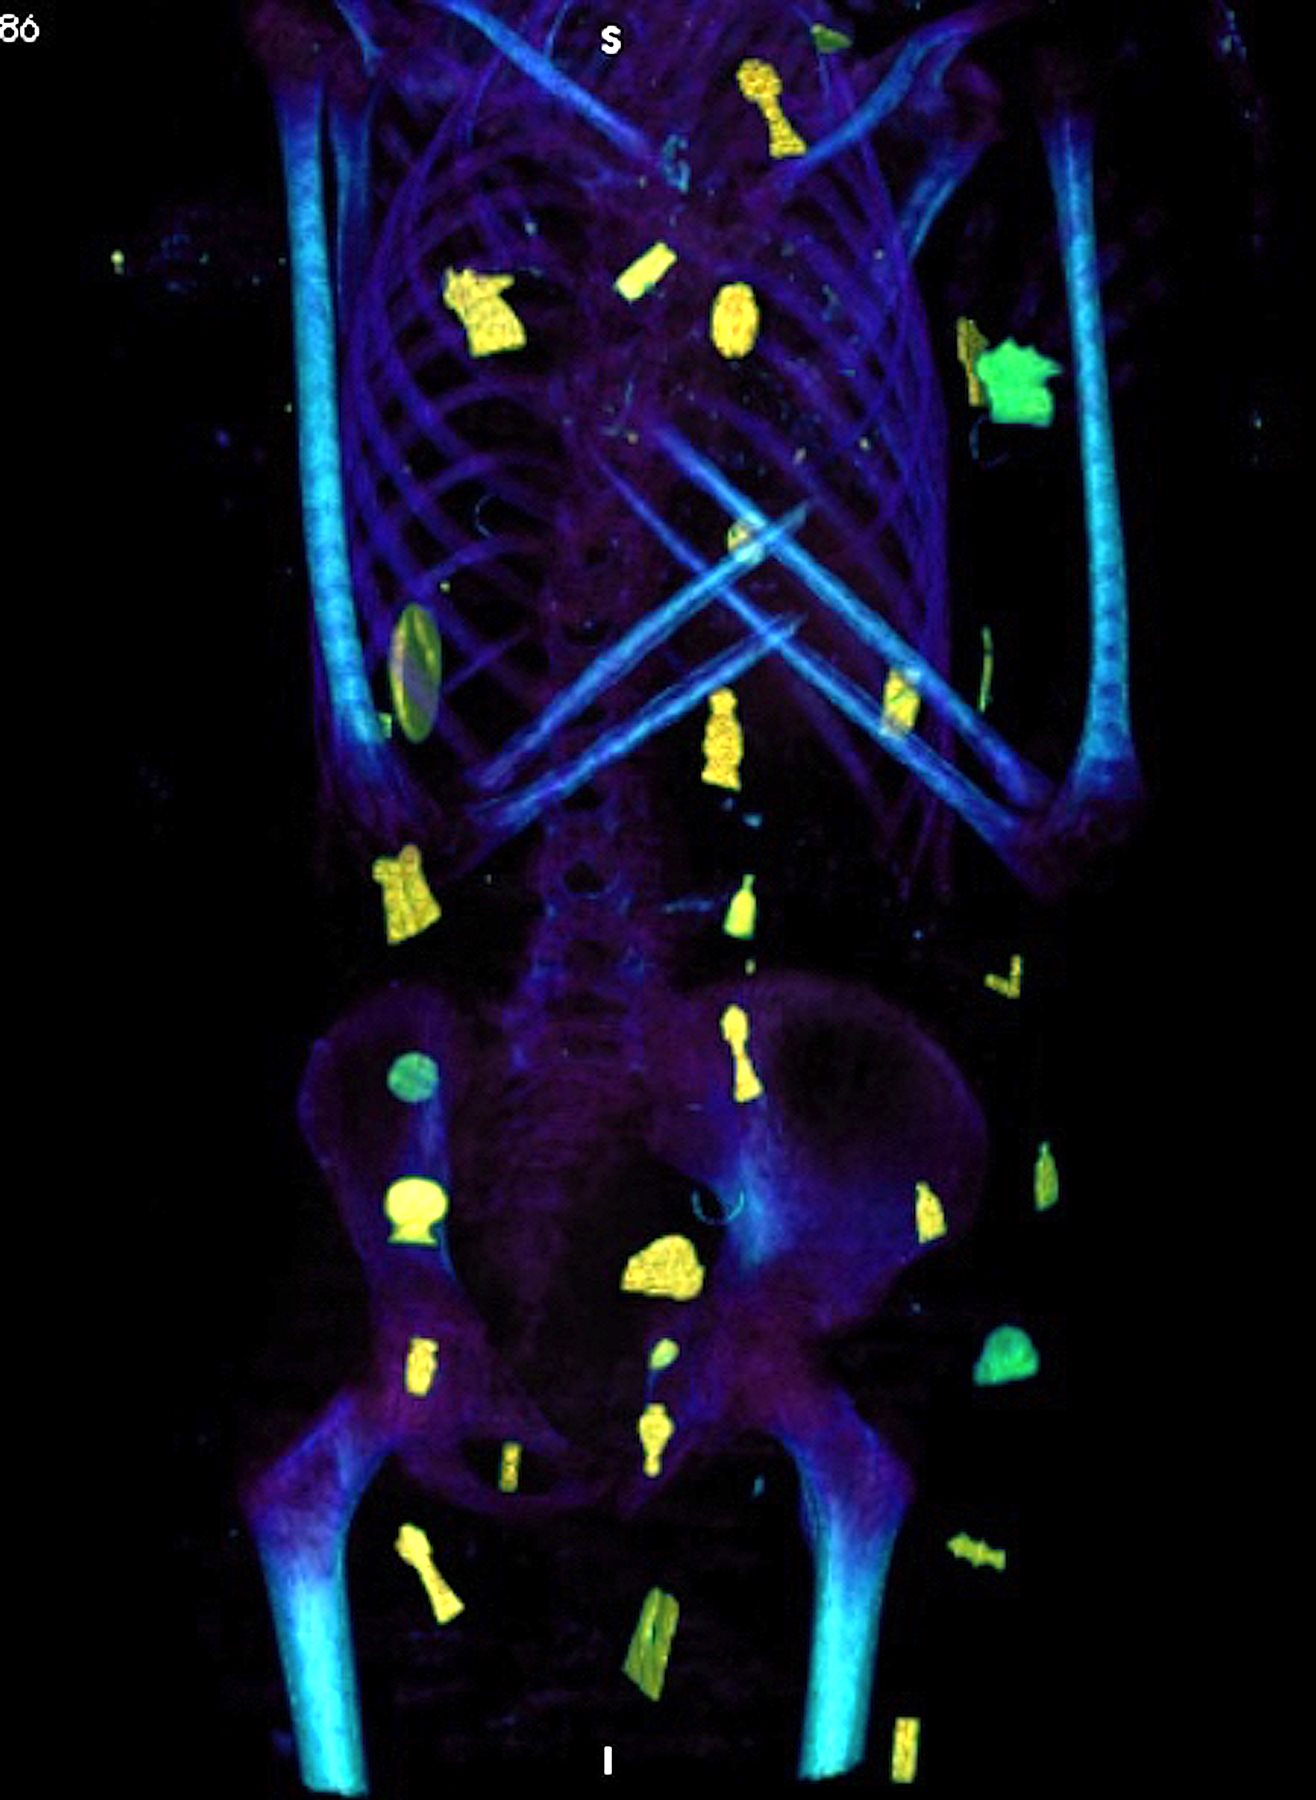

كما أوضحت صور الأشعات المقطعية الثنائية والثلاثية الأبعاد عن وجود حوالي 49 تميمة مرتبة ترتيبًا منمقًا في ثلاث أعمدة بين طيات اللفائف الكتانية وبداخل تجويف المومياء، كما أظهرت الأشعة أيضا 21 شكلًا مختلفًا للتمائم مثل عين المعبود حورس والجعران وتميمة الأفق والمشيمة وعقدة إيزيس والريشتان، وغيرهم.

ومن خلال نتائج قياسات الأشعة تبين أن 30 تميمة من التمائم المكتشفة داخل المومياء صنعت من الذهب بينما باقي التمائم صنعت من الأحجار أو الفيانس، بالإضافة إلى تميمة علي شكل لسان من الذهب وضعت بداخل فم المتوفي ليتمكن من التكلم في العالم الآخر، كما يوجد تميمة على شكل أصبعين أسفل الجذع لحماية فتحة التحنيط، وتميمة أخرى كبيرة من الذهب لجعران القلب موجودة بداخل تجويف صدر المومياء، والذي تم عمل مستنسخ منه باستخدام الطباعة ثلاثية الأبعاد.